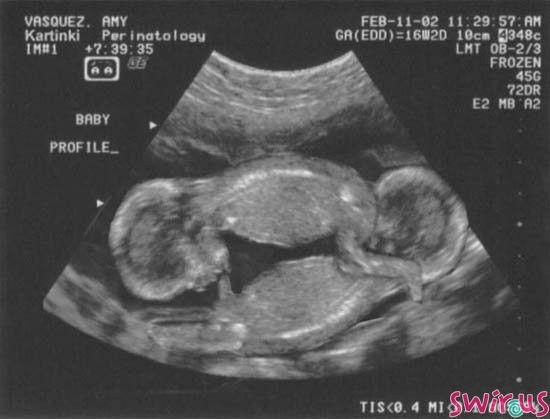

Trafiła do szpitala na łyżeczkowanie. Dobrze, że taki zabieg trwa tylko chwilę, a pobyt w szpitalu również ogranicza się do kilku godzin, bo umarłabym z tęsknoty z moją córeczką. Była jeszcze wtedy takim okruszkiem. Informacja, którą przekazał mi lekarz po zabiegu była okropna. Okazało się, że nosiłam w sobie jeszcze jedno dziecko. Tak, tak... byłam mamą bliźniaków dwu-jajowych. Jeden płód zatrzymał swój rozwój w 3 miesiącu. Miałabym dwójkę maluszków. Moje serce krwawiło, a jednak cieszyłam się, że mam zdrową córkę. Bitwa myśli, w mojej głowie była okropna. Największa radością był moment powrotu do domu i to, że mogłam przytulić Liwię. Byłam niesamowicie obolała i chociaż mama miała mi wtedy pomóc przy córci to chciałam, ją mieć tylko dla siebie. Nie chciałam pomocy, chciałam po prostu czuć, że jest i że jej nie stracę, tak jak moje drugie dziecko.